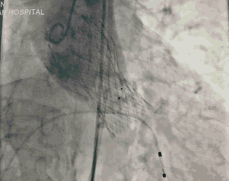

图3 TAVR瓣膜释放前造影

图4 TAVR球囊前扩张

图5 TAVR瓣膜释放后